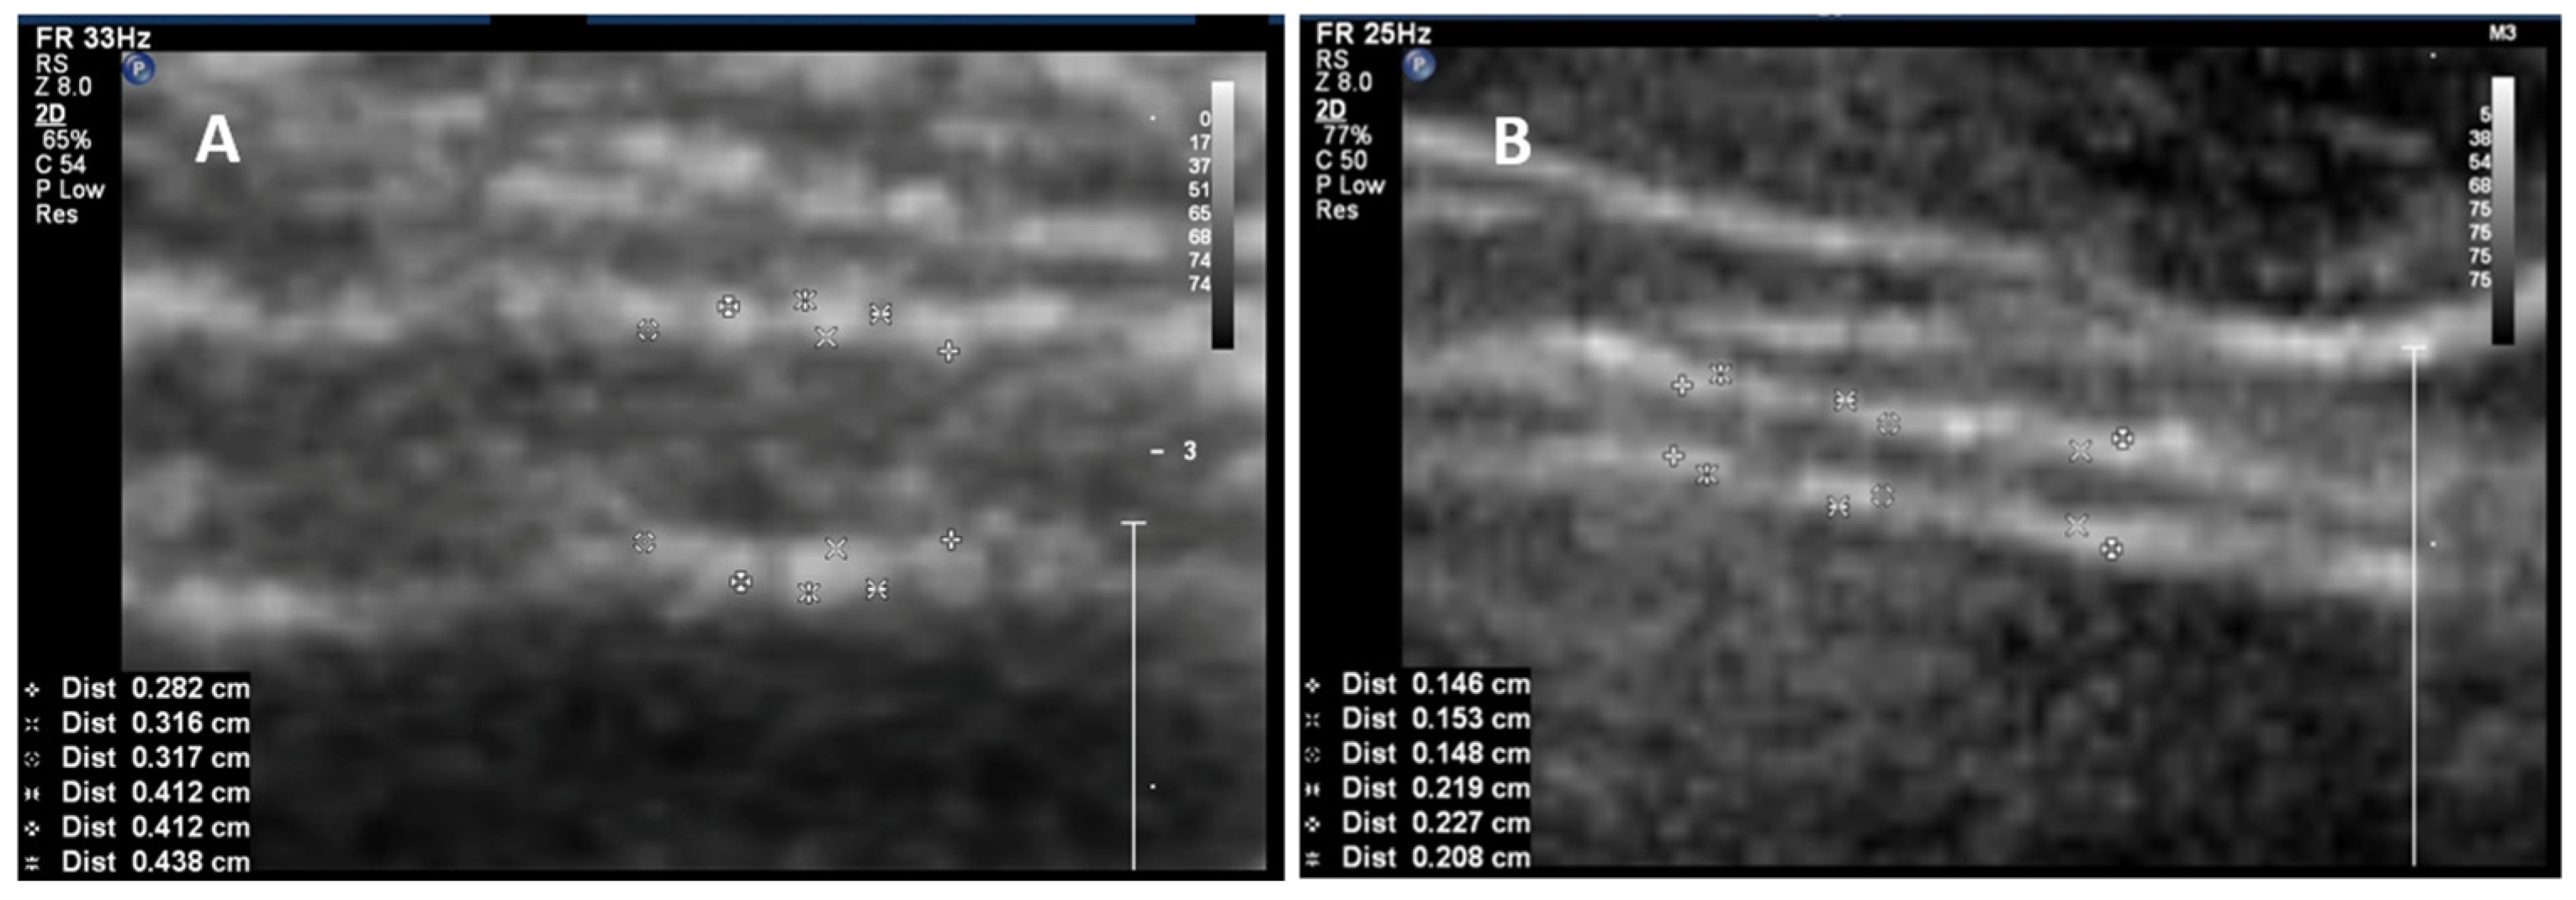

2. Bladder Wall Thickness in Relation to Bladder Filling Volume